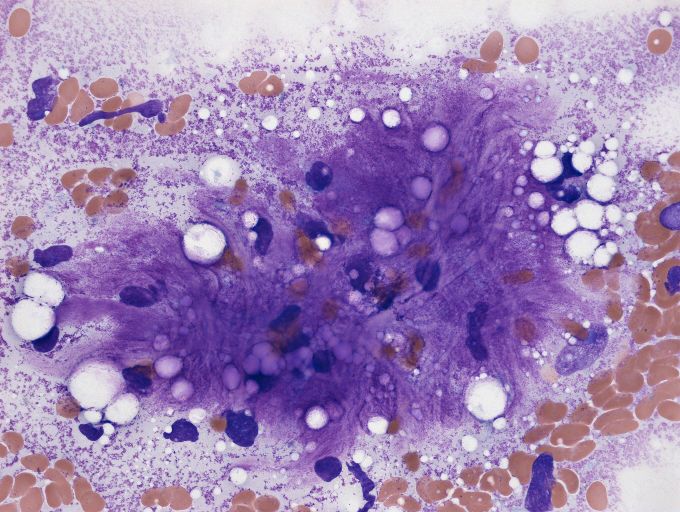

脂肪肉瘤是比较常见的一种软组织肉瘤,是成年人较常见的恶性软组织肿瘤,大约占全部软组织肉瘤的16%~21.4%,位居软组织肿瘤的第2位。

脂肪肉瘤好发的年龄大约在40~60岁左右,男女发病的几率相当,并没有特殊的性别差异, 发病的位置往往比较 深 ,多数位于 深部 的软组织内,可以起源于肌肉的筋膜或者是在我们身体深部血管丰富的部位四肢,尤其是 大腿和后腹膜 是两个极其好发的部位。

由于脂肪肉瘤来源于比较原始的间充质细胞,构成肿瘤的组织类型是比较复杂的,分化程度差别也比较大,所以它的临床生物学行为和预后也有特别大的差异。如果恶性程度低的,肿瘤可以局部复发,但不倾向于向远处转移,但如果是分化比较差的,恶性程度高的肿瘤复发的几率和转移的几率都比较高。